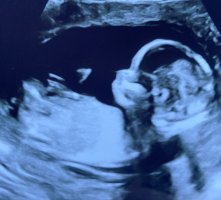

Noen som vil tippe? 13+1. JM klarte ikke si noe sikkert, har bestilt ny UL om 10 dager, kjenner jeg bare må vite

Ser ut som en jente

Dette må være en jente. Nub har ikke antydning til vinkel en gang.